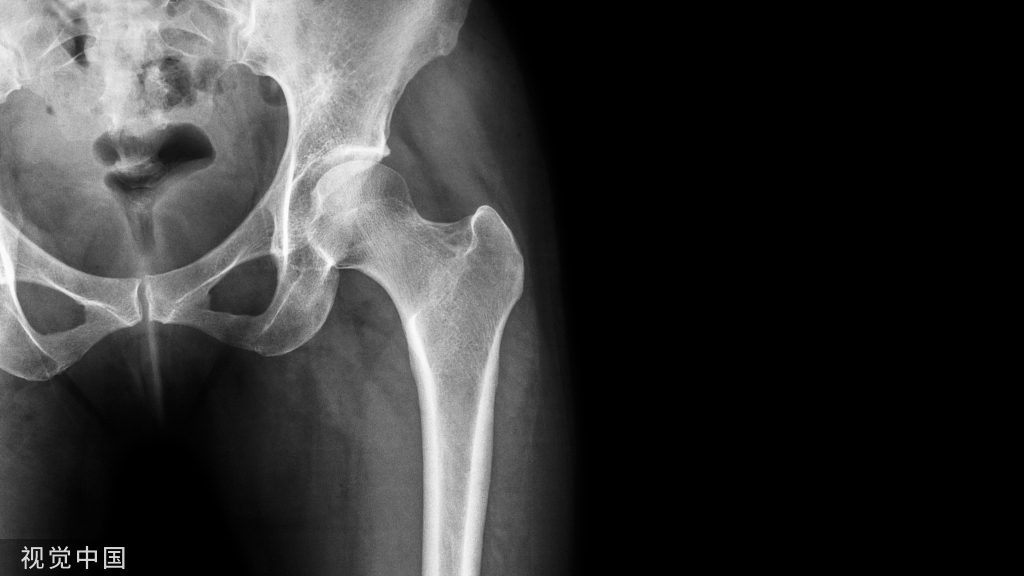

高角的II类下颌后缩,说明下颌骨发育不好。鉴别下颌骨生长发育的潜力要从以下几点来看:

髁状突颈部越粗,说明下颌骨发育越好;越细,说明下颌骨发育越差。

下颌骨正中联合越厚,说明下颌骨发育越好;越薄,说明下颌骨发育越差。

下颌角前切迹越小,说明下领骨发育越好:越深,说明下领骨发育越差。

下颌升支越宽,说明下颌骨发育越好:越窄,说明下颌骨发育越差。

下颌升支长轴倾斜角度越向下,说明下颌骨发育越好:越向前,说明下颌骨发育越差。